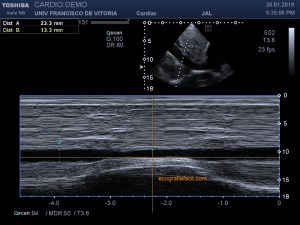

141. Mediciones de los planos paraesternales.